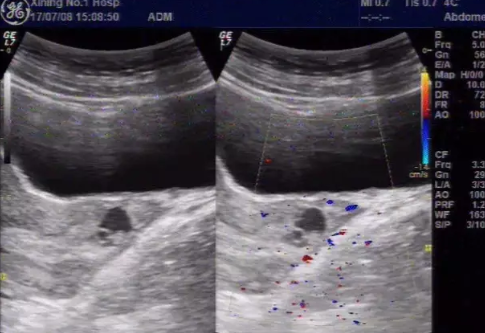

超聲檢查顯示,宮頸管內妊娠,子宮腔內無異物。多普勒超聲檢查能夠輔助區分宮頸妊娠和子宮內妊娠。組織學檢查證實,宮頸基質內存在絨毛。宮頸妊娠最有效的治療方案尚不明確。但是對于80-90%早期宮頸妊娠患者,肌內注射單或多劑量甲氨蝶呤是有效的。

臨床上診斷宮頸妊娠主要依靠經陰道的超聲檢查:

在宮頸內發現胎囊或胎盤

子宮內膜形態正常

子宮沙漏樣外觀和子宮頸管膨大